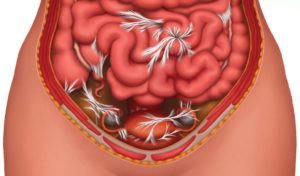

Колоноптоз – это состояние, при котором ободочная кишка опускается. Эта часть кишечника соединена с задней стенкой брюшной полости с помощью связок, и при их ослаблении или частичном разрыве кишка начинает провисать. Изменение нормального положения кишечника влияет на его функционирование, нарушает моторику и может приводить к симптомам частичной непроходимости, а также к каловой интоксикации.

Нарушение нормального расположения кишечника меняет активность кровотока: опустившийся орган создает непривычное давление на мочевой пузырь, яичники и матку у женщин, простату у мужчин. В результате постоянного аномального прессинга связки спазмируются, некоторые сосуды оказываются пережаты, возникают застойные явления.

При опущении отдельных участков кишечника создается повышенное давление на мочевой пузырь, предстательную железу у мужчин и половые органы у женщин. Такое состояние может существенно нарушить работу этих систем. Частое давление может вызывать спазмы связок, так как сжимается просвет кровеносных сосудов, находящихся в этой области.